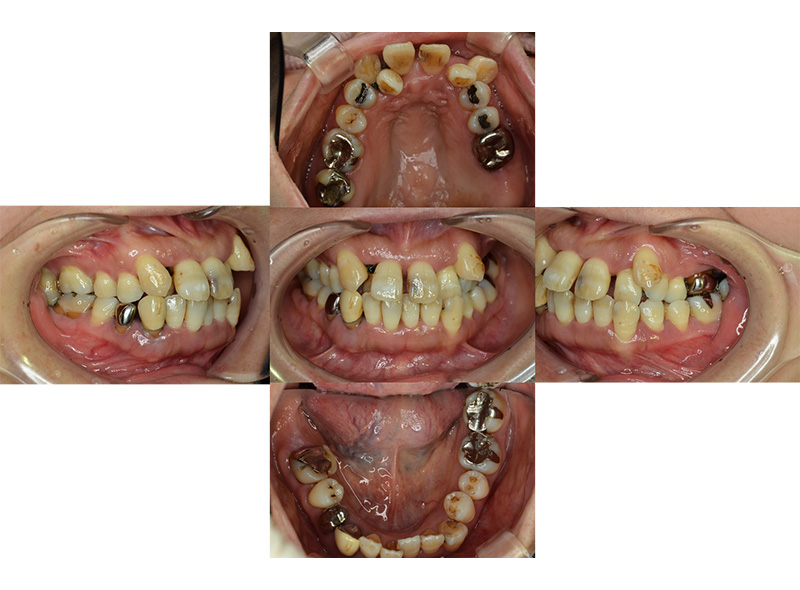

歯周再生療法 精密根管治療 歯周矯正治療 ジルコニアセラミック治療

Before

After

治療期間・回数

約3年・約20回

費用

1,400,000円(歯周矯正治療も含む)

治療のリスク

詰め物・被せ物の調整が難しく、割れた場合は再治療が必要。